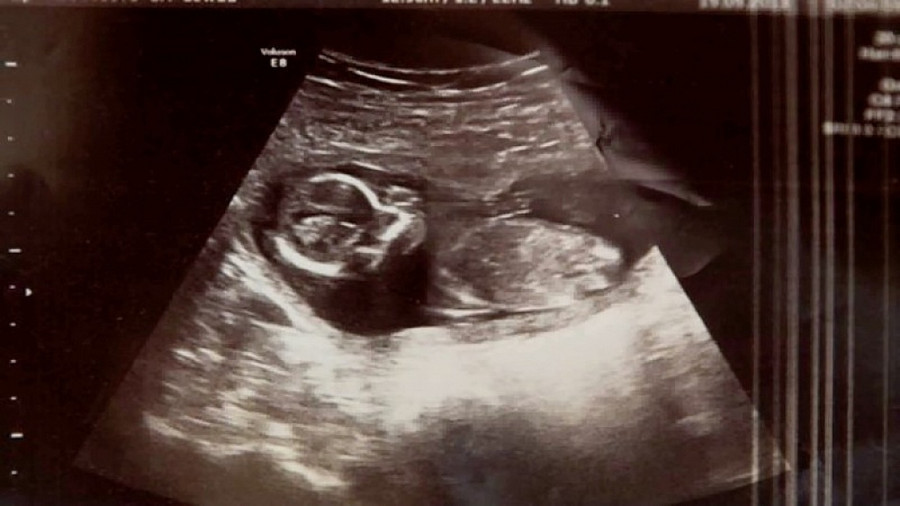

Các bác sĩ tại bệnh viện Rotunda, Dublin đã kiểm tra Michelle một lần cuối trước khi nạo vét và phát hiện nhịp tim đập ngay trong tử cung của bà mẹ – Michelle vẫn đang mang thai!…

“Không thể tin được, chúng ta có nhịp tim đập“, vị bác sĩ trẻ bối rối giải thích với một đồng nghiệp già hơn vừa được gọi tới. Hạnh phúc lại mỉm cười với Michelle một lần nữa.

Hóa ra, bà mẹ Michelle đã mang thai song sinh, và cô mới chỉ mất có một đứa trẻ. Đứa trẻ còn lại đã bị che khuất bởi máu và dịch do vụ sảy thai, khiến cho các bác sĩ không thể xác định được em trong quá trình siêu âm.